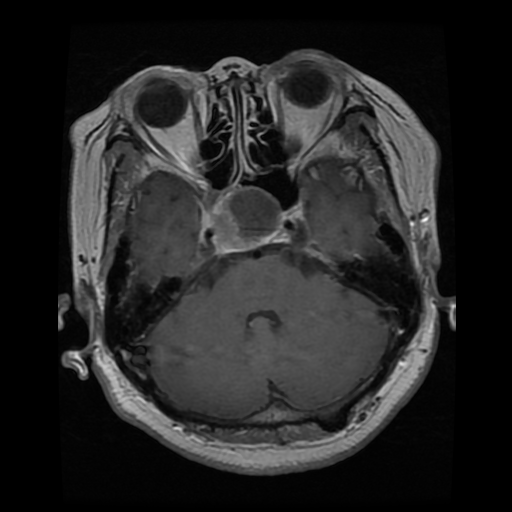

To validate the zero-shot and weakly supervised segmentation results, as well as different design components of the MedCLIP-SAM framework, we used three public datasets (three different modalities) with segmentation ground truths (segmentation of breast tumor, brain tumor, and lung), which were split for training, validation, and testing. These datasets with their divisions include:

• Brain Tumor MRI: Brain Tumor dataset from [10] consisting of 1,462, 400, and 400 T1-weighted MRIs for training, validation and testing respectively.

In Table 3, we present segmentation accuracy for our proposed method in zero-shot and weakly supervised settings, with fully supervised segmentation as a reference. Note that for zero-shot results, we include a comparison between initial labels generated by gScoreCAM-based saliency maps (“Saliency Maps”) and pseudo-masks from SAM (“Saliency Maps + SAM”). Combining BiomedCLIP and SAM demonstrates clear advantages, notably improving segmentation quality for all metrics (p<0.05𝑝0.05p<0.05). Comparing zero-shot results to weakly supervised segmentation, we observe general improvements for X-ray-based lung segmentation. However, the impact on tumor segmentation in breast ultrasound and brain MRI remains unclear, with an AUC boost of similar-to\sim2% only for breast ultrasound. While fully supervised DL models currently provide state-of-the-art accuracy for medical image segmentation, our MedCLIP-SAM zero-shot segmentation outperformed ResUNet-based full supervision for breast ultrasound and brain MRI segmentation. Lung X-ray segmentation, however, showed superior accuracy with the fully supervised method across all metrics. Finally, to provide a qualitative assessment, exemplary segmentation results for zero-shot and weakly supervised settings are shown in Fig. 2 against the original image and ground truths (GTs) across all segmentation tasks.